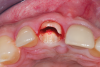

Fig 4. Preoperative CBCT cross-sectional view demonstrating very thin buccal cone.

Figure 4